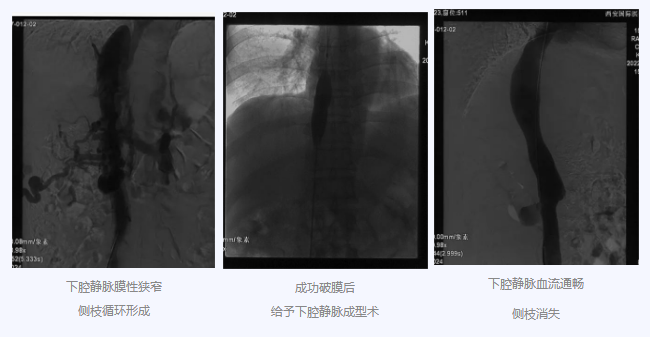

入院后,在韓國宏院長的安排下,臨床經(jīng)驗(yàn)豐富的醫(yī)師給老謝做了B超、CT 等檢查,結(jié)果顯示:三支肝靜脈近心端閉塞,肝內(nèi)側(cè)枝循環(huán)形成,下腔靜脈近心房入口處隔膜樣狹窄,隨后的DSA血管造影也證實(shí):下腔靜脈狹窄,且有側(cè)枝形成,最終確診困擾老謝20年的疾病為混合型布加綜合征,是一種罕見病。

明確診斷后,韓院長帶領(lǐng)團(tuán)隊縝密分析老謝的病情,為其制定最佳的治療方案,考慮到老謝的根本病因是下腔靜脈阻塞,介入手術(shù)成為首選治療方法,通過微創(chuàng)介入手術(shù),可準(zhǔn)確打通患者的閉塞血管,癥狀迅速緩解。做好充分術(shù)前準(zhǔn)備后,為患者行“下腔靜脈成型術(shù)”,精準(zhǔn)定位快速貫通,閉塞的下腔靜脈順利開通,手術(shù)圓滿完成。